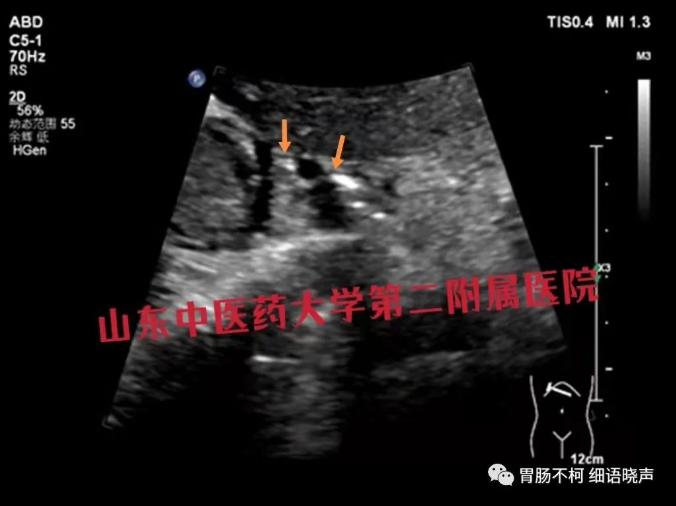

病例一,自黏膜上皮线起始至肿块,胃壁超声七层显示了强(LI)-低(L2)-强(L3)-低(L4)-强(部分L5)五层线,强烈提示肿块跟L5(黏膜下层)关系密切,结合肿块长轴与胃壁长轴一致的特点,超声首诊胃淋巴瘤,病理免疫组化结果证实: